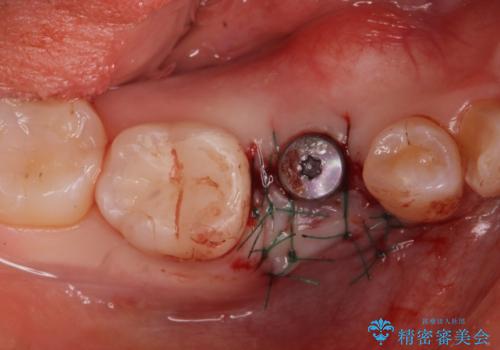

インプラント治療

- 過去に抜けてしまった歯のところにインプラントを入れたいとの事で来院。

CTで確認したところ骨の高さや厚みがインプラント埋入できる状態でしたのでインプラント治療を行いました。

併用して銀歯も気になるとの事でしたのでセラミック治療も行いました。